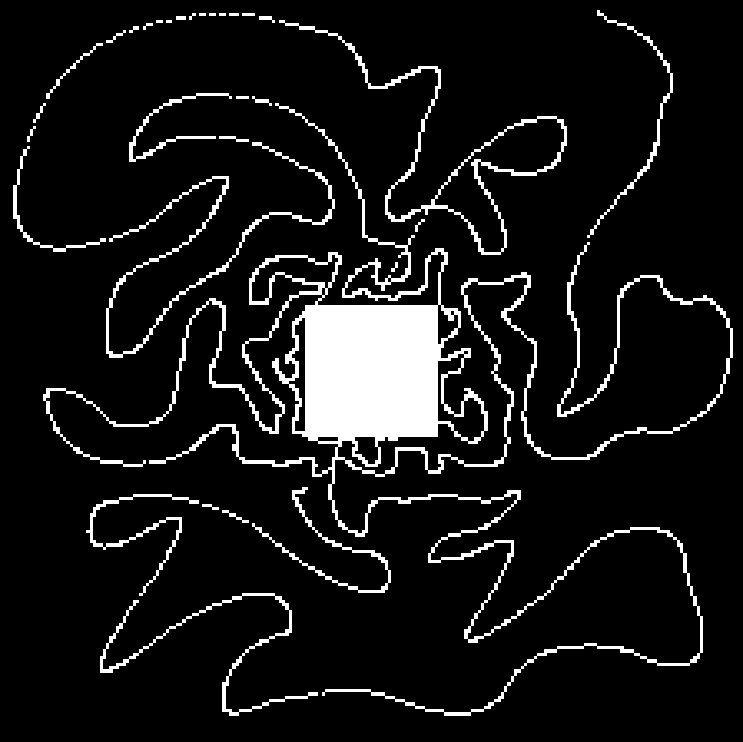

Compressed Sensing (CS) provides a theoretical framework to justify the downsampling of -space (2D or 3D Fourier domain) in Magnetic Resonance Imaging (MRI). CS-MRI is usually based on independent random drawing of -space locations according to a prescribed density. From recent theoretical works [3, 4], one can derive an optimal sampling density that reduces at most the number of samples collected in MRI without degrading the image quality at the reconstruction step [5, 6]. In [7], simulations show that distributions with radial decay (see Fig. 1(a)) with full -space center acquisition perform better in numerical experiments.

However, such sampling schemes are not performed along continuous lines and thus not physically plausible in MRI because of the constraints involved on the magnetic field gradient (magnitude and slew-rate). In [8], we have proposed a new approach to design continuous sampling trajectories based on the solution of Travelling Salesman Problem (TSP), as illustrated in Fig. 1(b). The specificity of this approach is that the empirical distribution of the trajectory can approximate any prescribed distribution . Such a curve is called a -Variable Density Sampler (-VDS). Unfortunately, continuity of the sampling trajectory is not a sufficient condition in MRI and it is not clear how to design admissible gradient waveforms to traverse such a trajectory.

| (a) | (b) |

|---|---|

|

|